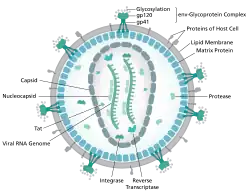

Estrutura e genoma

A estrutura do VIH é diferente da de outros retrovírus. É aproximadamente esférica e com um diâmetro de cerca de 120 nm, cerca de 60 vezes menor que um glóbulo vermelho, ainda que grande para um vírus.[20][21] É composto por duas cópias de ARN positivo de cadeia única de senso positivo com aproximadamente 9749 nucleotídeos[22] que codifica os nove genes do vírus, envolto por um capsídeo cónico composto de 2 milcópias da proteína viral p24.[23] O ARN de cadeia único está intimamente ligado às proteínas da nucleocapside, p7, e às enzimas necessárias ao desenvolvimento do virião como a Transcriptase reversa, a aspartate protease, ribonuclease e integrase. O capsídeo é envolto por uma matriz composta pela proteína viral p17, assegurando a integridade da partícula do virião.[23]

Este conjunto é por sua vez envolto pelo envelope viral, que é composto por duas camadas de moléculas gordas denominadas fosfolípidos, obtidas a partir da membrana de uma célula humana quando uma partícula viral recém-formada brota da célula. No envelope viral estão incorporadas proteínas da célula anfitriã e cerca de 70 cópias de uma proteína complexa do VIH que é proeminente na superfície da partícula viral.[23] Esta proteína, conhecida por Env, consiste num conjunto de três moléculas denominadas glicoproteína (gp) 120, e uma haste que consiste em três moléculas gp41 que ligam a estrutura ao envelope viral.[24] Este complexo glicoproteico permite ao vírus ligar-se e fundir-se com as células-alvo de modo a dar início ao ciclo de infeção.[24] Estas duas proteínas de superfície, sobretudo a gp120, têm vindo a ser identificadas como o alvo de futuros tratamentos ou vacinas contra o VIH.[25]

O genoma de ARN consiste em pelo menos sete marcos estruturais (LTR, TAR, RRE, PE, SLIP, CRS e INS) e nove genes ('gag, pol, and env, tat, rev, nef, vif, vpr, vpu, e por vezes um décimo tev, que consiste numa fusão de tat, env e rev), codificando 19 proteínas. Três destes genes, gag, pol e env, contêm a informação necessária para produzir as proteínas estruturais de novas partículas virais.[23] por exemplo, o env codifica uma proteína denominada gp160 que é quebrada por uma protease celular de modo a formar gp120 e gp41. Os restantes seis genes, 'tat, rev, nef, vif, vpr, e vpu (ou vpx no caso do VIH-2), são genes reguladores para proteínas que controlam a capacidade do VIH em infectar céulas, produzir novas cópias de si mesmo (replicar-se) ou provoca a doença.[23]